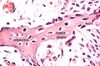

Osteócitos

Onde encontrar na lâmina?

Interior da matriz óssea.

A principal função dos osteócitos é realizar a manutenção da…

matriz óssea.